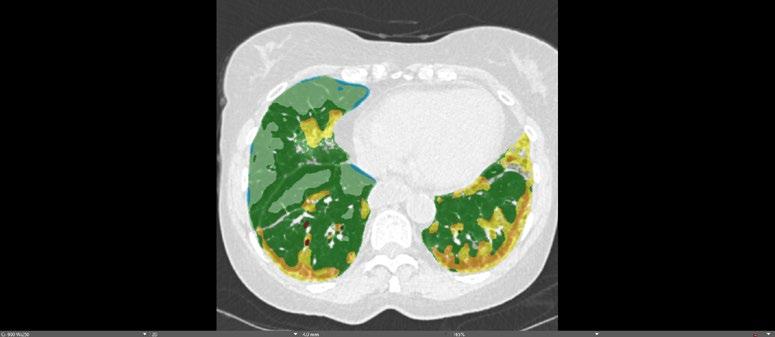

Radiogenomics Relationship of Nonsmall Cell Lung Cancer: Preliminary Results

BACKGROUND AND AIMS

Radiomics, an emerging paradigm in medical imaging, entails the quantitative analysis of tumour features, and has exhibited potential in predicting treatment responses and outcomes. Furthermore, within the domain of -omics assessments, the significance of comprehensive genetic evaluation in non-small cell lung cancer (NSCLC) is on the rise, influenced by both biological and therapeutic considerations.

The aim of this study was to correlate radiomics features with the genetic results obtained from liquid biopsy in patients with lung tumours. The prediction of tumour genetics in radiomics relies on the presumption of conducting a non-invasive evaluation of molecular characteristics in tumour tissues, which can be challenging in certain tumour types, such as NSCLC. Therefore, in this context, the authors considered it pertinent to explore and generate hypotheses regarding the technical feasibility of identifying associations between genomics acquired through liquid biopsy assessments and radiomics.

MATERIALS AND METHODS

This observational, prospective study integrated radiomic perspectives using CT and genomic perspectives, through next-generation sequencing applied to liquid biopsies.

The authors included 62 patients with NSCLC who underwent pre-surgery CT (Revolution™ 128 MDCT, GE HealthCare, Chicago, Illinois, USA) at the Radiology Department of Campania University Luigi Vanvitelli, Naples, Italy. Every patient for whom liquid biopsy was performed gave informed consent for the genetic analysis. For the radiomic analysis, image processing CT volumes were manually delineated using ITK-SNAP 3.8.0 (University of Pennsylvania, Philadelphia, USA). Radiomics features (first order: Gray Level Co-occurrence Matrix, Gray Level Run Length Matrix, Gray Level Size Zone, Gray Level Dependence Matrix, and Neighbouring Gray Tone Difference Matrix) were computed using Pyradiomics1 in Python 3.7 (Python Software Foundation, USA) environment.

Radiomic features were derived from CT images, and genetic assessments were performed using a comprehensive panel targeting 523 cancerrelated genes. For the statistical analysis, association between radiomic features and gene mutations were assessed using feature importance based on receiver operating characteristic curve analysis; moreover, a machine learning approach based on support vector machine was used to evaluate the ability of radiomic features to predict gene mutations.

Associations between radiomic features and genetic mutations were established using the area under the receiver operating characteristic curve. Machine learning techniques, including support vector machine classification, aimed to predict genetic mutations based on radiomic features. The prognostic impact of selected gene variants was assessed using Kaplan–Meier curves and log-rank tests.

RESULTS

Sixty-two patients underwent screening, with 53 being comprehensively characterised radiomically and genomically. This group was predominantly male (68.4%), and adenocarcinoma was the prevalent histological type (73.7%). Most patients exhibited ECOG Performance Status of 0 or 1 (87.7%), and 91.2% had a history of former or current smoking. Disease staging was distributed across I–II (38.6%), III (31.6%), and IV (29.8%). Significant correlations were identified with mutations

Abstract ● ECR 2024 24 Radiology ● April 2024 ● Creative Commons Attribution-Non Commercial 4.0

of ROS1 p.Thr145Pro (shape_Sphericity), ROS1 p.Arg167Gln (glszm_ZoneEntropy, firstorder_TotalEnergy), ROS1 p.Asp2213Asn (glszm_GrayLevelVariance, firstorder_ RootMeanSquared), and ALK p.Asp1529Glu (glcm_Imc1). Patients with the ROS1 p.Thr145Pro variant demonstrated markedly shorter median survival compared to the wild-type group (9.7 months versus not reached; p=0.0143; hazard ratio: 5.35; 95% confidence interval: 1.39–20.48).

CONCLUSION

This study contributes to advancing the prediction of cancer genetics through the application of non-invasive radiomic techniques. The prediction of tumour genetics in radiomics hinges on the assumption of conducting a non-invasive assessment of molecular characteristics in tumour tissues, which can pose challenges in certain tumour types, such as NSCLC. Therefore, within this context, the authors deemed it relevant to explore and formulate hypotheses regarding the technical feasibility of identifying associations between genomics obtained through liquid biopsy assessments and radiomics.

Specific radiomic features illustrate the capability to predict non-synonymous mutations of ROS1 and ALK in patients with NSCLC. Investigating the prediction of cancer genetics using non-invasive radiomic techniques represents an innovative frontier in scientific research, which is currently undergoing extensive investigation. Research on the use of conventional CT features and CT image-based radiomic features to predict the gene mutation status of lung cancer is still in its nascent stages.

The integration of radiomic techniques in predicting cancer genetics holds potential, but is constrained by cost and technological limitations. Despite these challenges, the authors’ study explores the relationships between genomics and radiomics, revealing specific genetic variants associated with radiomic features. While acknowledging limitations, particularly the small sample size and the lack of actionable mutations, this research lays the groundwork for broader investigations aiming to link radiomics and genomics in NSCLC. The ultimate objective is to improve prognostic accuracy and refine therapeutic strategies. ●